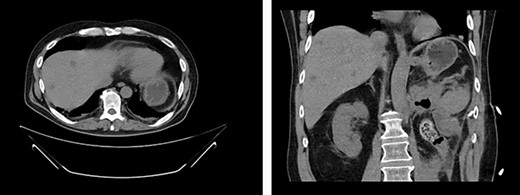

Appearance of effusion in the left retroperitoneal space in transverse (left) and coronal (right) planes on CT; it can be seen encroaching on the spleen; subsequent cytology ruled of malignant effusion.

Two weeks post-resection, the patient was recovering as expected. At 4 weeks post-resection, radiation oncology recommended 7 weeks of intensity-modulated radiation therapy to both the surgical site and at-risk nodes identified on CT. Six weeks post-resection, the patient presented to the ED with nausea and vomiting. Abdominal CT revealed a retroperitoneal effusion at the surgical site (Fig. 3). At this admission, the patient also tested positive for COVID-19, delaying drain placement and his radiation treatments for 2 weeks.